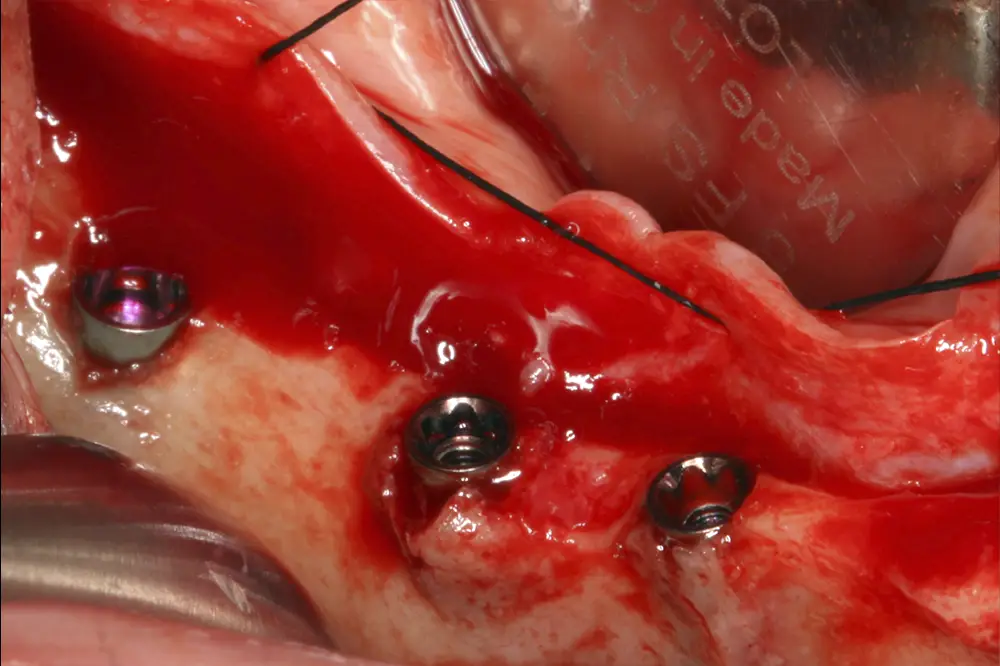

Figuras 16 y 17. Implantes colocados tras la cirugía.